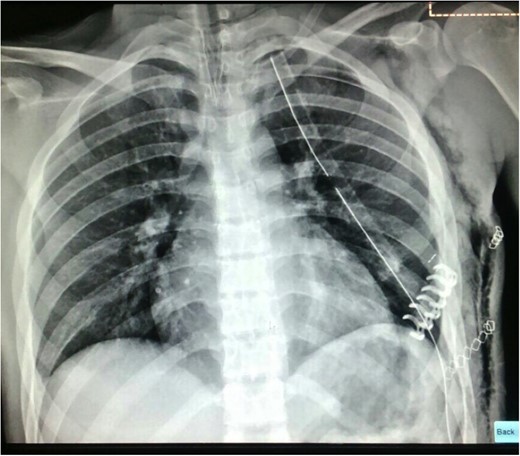

A longitudinal incision was made over the fractured rib (Fig. 4). A displaced rib fracture was observed. Bone segments were reduced and fixed using a 6 cm titanium plate (STRATOSTM System). A chest tube was inserted through the seventh ICS and connected to a closed water seal device on suction (Fig. 5).